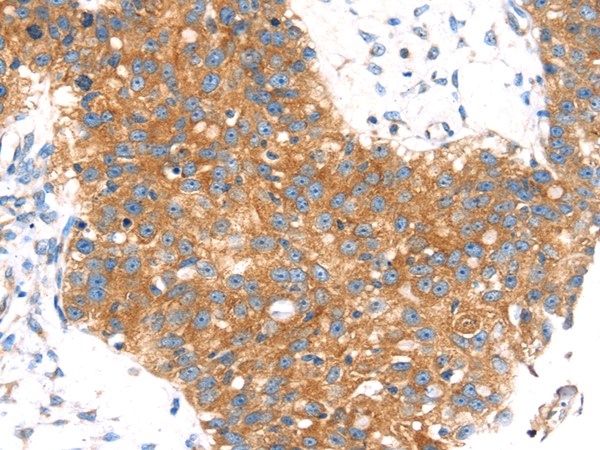

分类: 科研抗体货号: P10645别名: AM2; dJ579N16.4应用: IHC反应种属: Human, Mouse, Rat